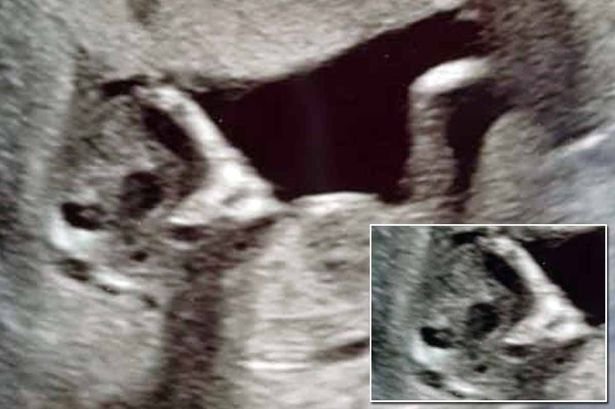

Gëzimi që mbante në bark një bebe të shëndetshme u kthye në panik, kur partneri i tha Sophie Scott se imazhi i marrë nga ekoja, i ngjante një krijese aliene.

Stephen Roberts, 24 vjeç dhe Sophie, 16-vjeçe ishin të sigurt që mjekët nuk kishin dalluar binjakun tjetër.

“Mund të shihnim një palë sy të tjerë përtej bebes dhe koka kishte formën e një alieni”, tha studentja nga South Shields, Tyneside në Angli.

Ndonëse bënin shaka, dy të rinjtë ishin disi të frikësuar pasi askush nuk mund t’i jepte përgjigje se çfarë ishte. Megjithatë, 4 javë më vonë, ekoja tjetër shfaqte një bebe normale dhe brenda barkut të 16-vjeçares nuk kishte jetë aliene.